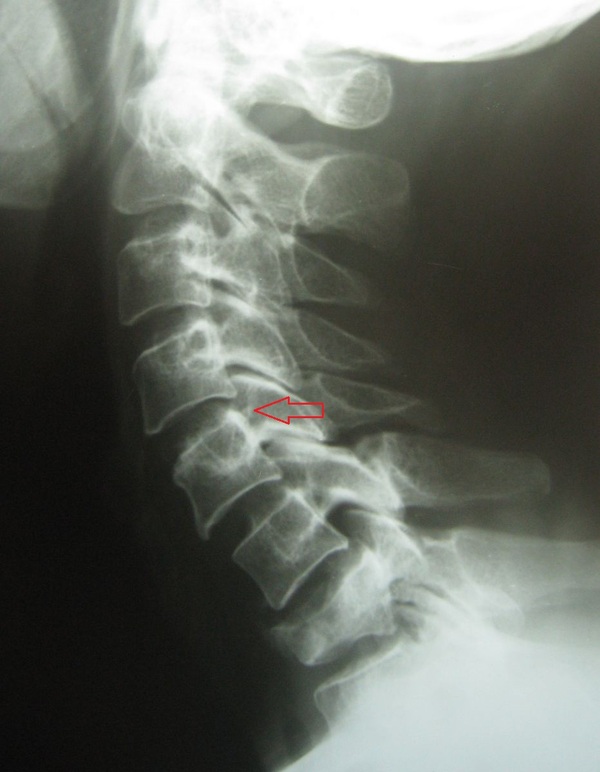

Нестабильность в шейном отделе позвоночника – это функциональное отклонение, вызванное патологической мобильностью в шейном отделе позвоночника, которая проявляется локальным увеличением амплитуды движений, смещением тел позвонков относительно суставной оси и появлением избыточной свободы.

Вот достаточно неплохое определение. При переводе на общечеловеский язык получается, что нестабильность - это некоторое болтание одного позвонка (вышележащего) относительно другого (нижележащего) с возвращением позвонка в своё штатное место.

Самые внимательные могут заметить, что с 7 шейным позвонком случилась неприятность похожая на компрессионный перелом, поэтому можно предположить, что в данном случае нестабильность травматическая.

Листез или спондилолистез – это смещение структур позвоночника, а именно вышележащего позвонка относительно нижележащего.

Диагностика проблемы проста и бесславна. В любой участковой поликлинике по месту жительства, снабженной работающей рентген-установкой, вы можете пройти рентгенографию шейного и/или поясничного отделов позвоночника с функциональными пробами по направлению вашего терапевта или другого врача. Это всегда 4 снимка, например: прямая шея в прямой проекции, прямая шея в боковой проекции, сгибание шеи в боковой проекции, разгибание шеи в боковой проекции. Поясница аналогично.